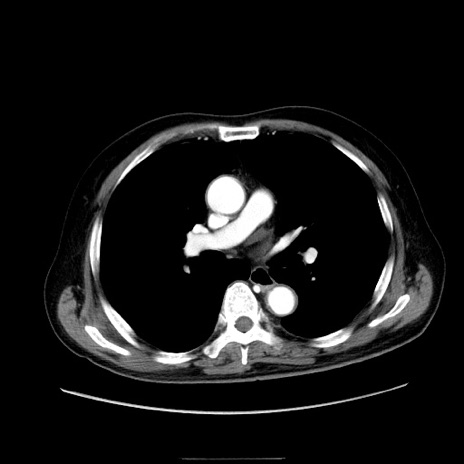

症例30(横断像)

【症例】80歳代男性

【主訴】臍周囲痛

【現病歴】約6時間前から臍下部痛が出現。次第に腹部膨隆・背部痛も生じてきたため来院。背部痛の場所は変化しない。

【身体所見】意識清明、BT 36.3℃、BP  131/87mmHg、P 87bpm、SpO2 100%(RA)、臍周囲自発痛・圧痛あり、反跳痛なし、自発痛部位に一致して板状硬あり、腹部膨隆、腸雑音減弱、CVA tenderness両側陰性。